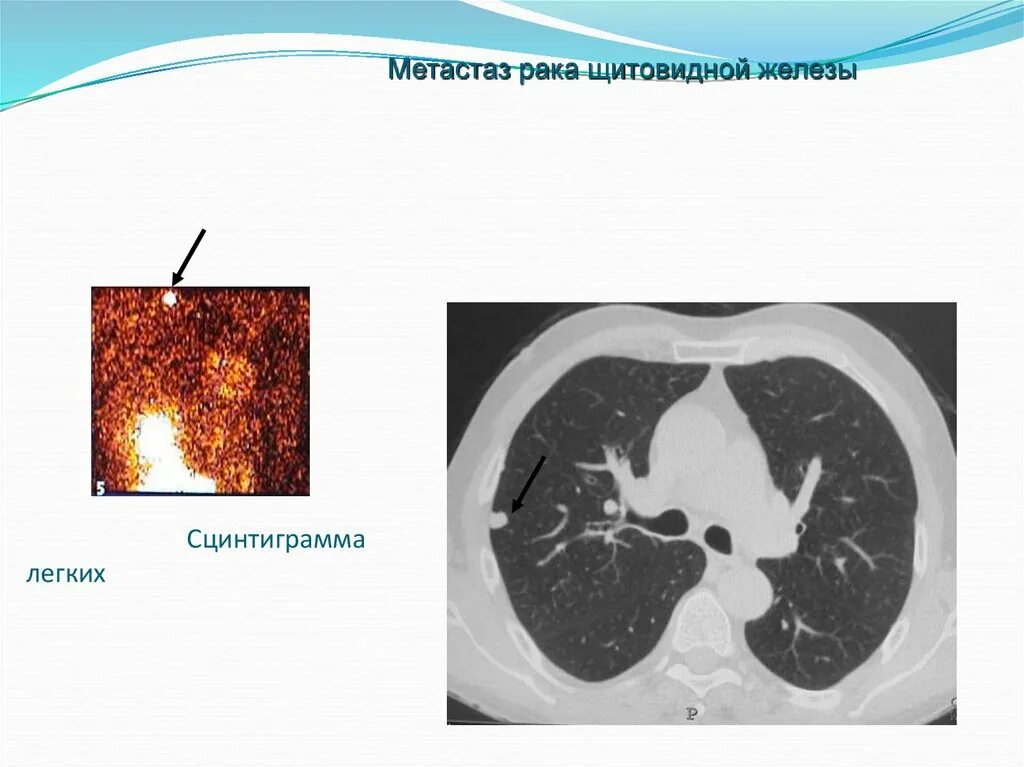

Лучевая при раке легких